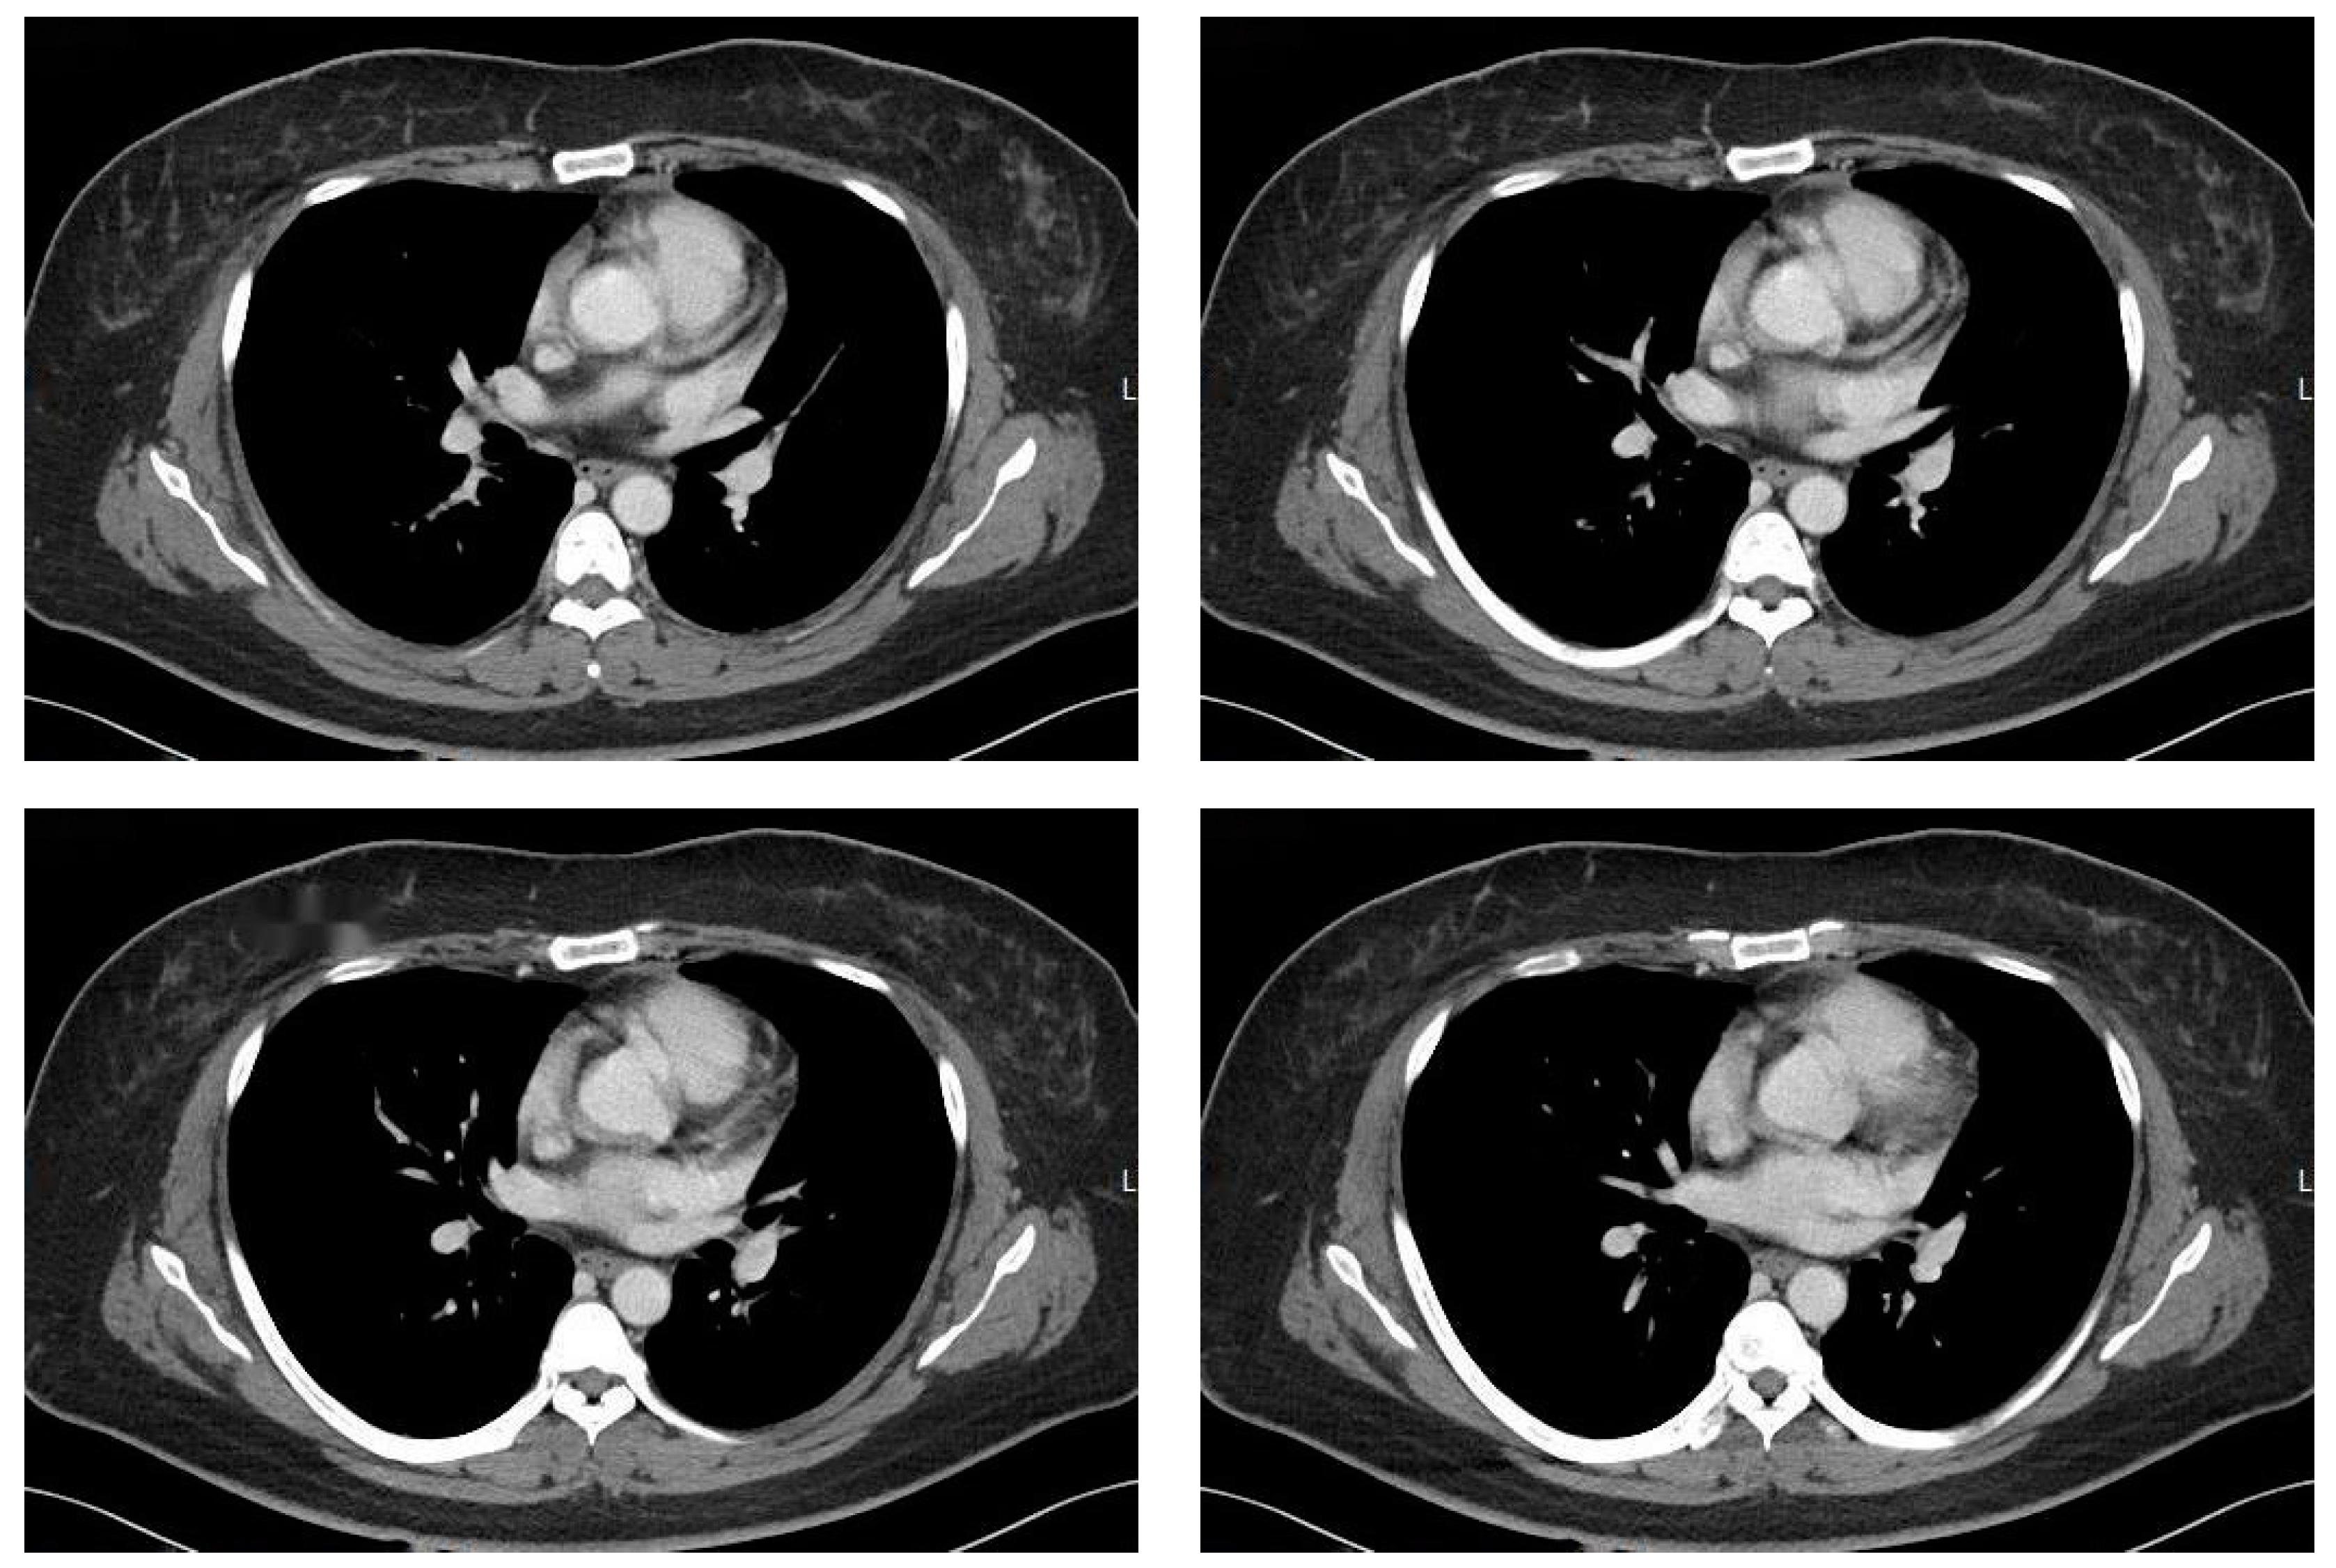

- Shi, J.; Bao, G.; Hong, J.; Wang, S.; Chen, Y.; Zhao, S.; Gao, A.; Zhang, R.; Hu, J.; Yang, W.; et al. Deciphering CT texture features of human visceral fat to evaluate metabolic disorders and surgery-induced weight loss effects. eBioMedicine 2021, 69, 103471. [Google Scholar] [CrossRef]

- Dadson, P.; Rebelos, E.; Honka, H.; Juárez-Orozco, L.E.; Kalliokoski, K.K.; Iozzo, P.; Teuho, J.; Salminen, P.; Pihlajamäki, J.; Hannukainen, J.C.; et al. Change in abdominal, but not femoral subcutaneous fat CT-radiodensity is associated with improved metabolic profile after bariatric surgery. Nutr. Metab. Cardiovasc. Dis. 2020, 30, 2363–2371. [Google Scholar] [CrossRef]